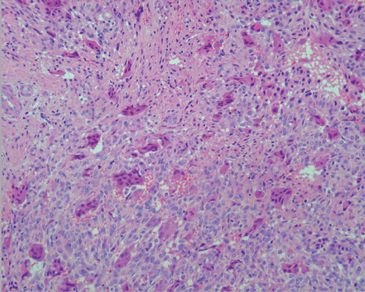

Las biopsias de clavícula y tibia derecha mostraron proliferación fibrohistiocítica de tipo benigno (Figura 1), por lo que es derivado a Endocrinología para descartar posible hiperparatiroidismo.

Figura 1. Tumor pardo caracterizado por una proliferación fibrohistiocítica vascularizada y con células gigantes multinucleadas de tipo osteoclasto. (Tinción Hematoxilina- Eosina. Ampliación 40X).

Su aspecto histológico característico consiste en la presencia de lesiones osteolíticas asociadas a células gigantes multinucleadas y fibrosis peritrabecular progresiva. Estas alteraciones son secundarias al incremento de la actividad osteoclástica y corresponden a la etapa terminal de la remodelación ósea que ocurre debido al hiperparatiroidismo3,5.